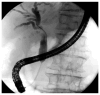

This review aims to focus on what we know about the management of biliary strictures of unknown etiology, especially exploring our diagnostic armamentarium in the setting of indeterminate biliary strictures. Presently, this is a current issue that has a relevant impact both on patient prognosis, often delaying diagnosis, and on overall costs associated with repeating diagnostic procedures, sometimes performed with very expensive devices. We also focus on current biliary drainage approaches, providing an overview of therapeutic options, endoscopic or not.

Keywords: ERCP; EUS; cholangiocarcinoma; cholangioscopy; strictures.